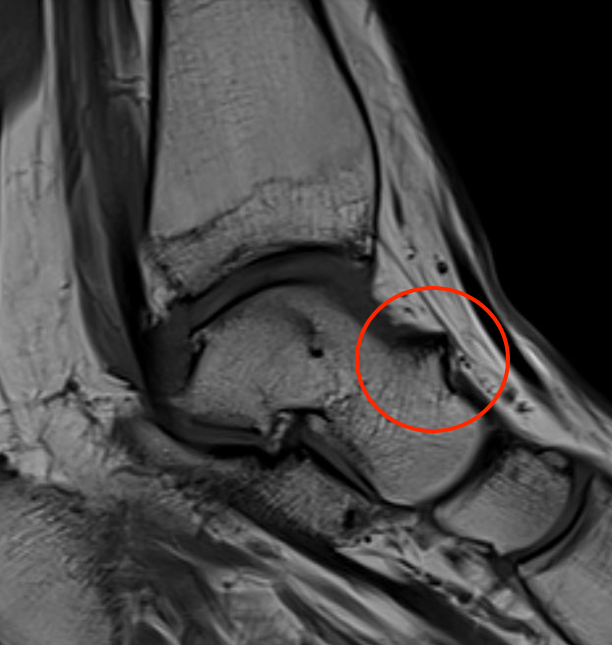

Impingement between anterior distal tibial osteophyte and sulcus of the talus in dorsiflexion

Anterior osteophytes

Soft tissue impingement - scar tissue in anterolateral gutter from recurrent ankle sprains

Bassett's ligament - thickened fascicle of the AITFL

Anterior tibial and talus spurs with normal joint space

MRI